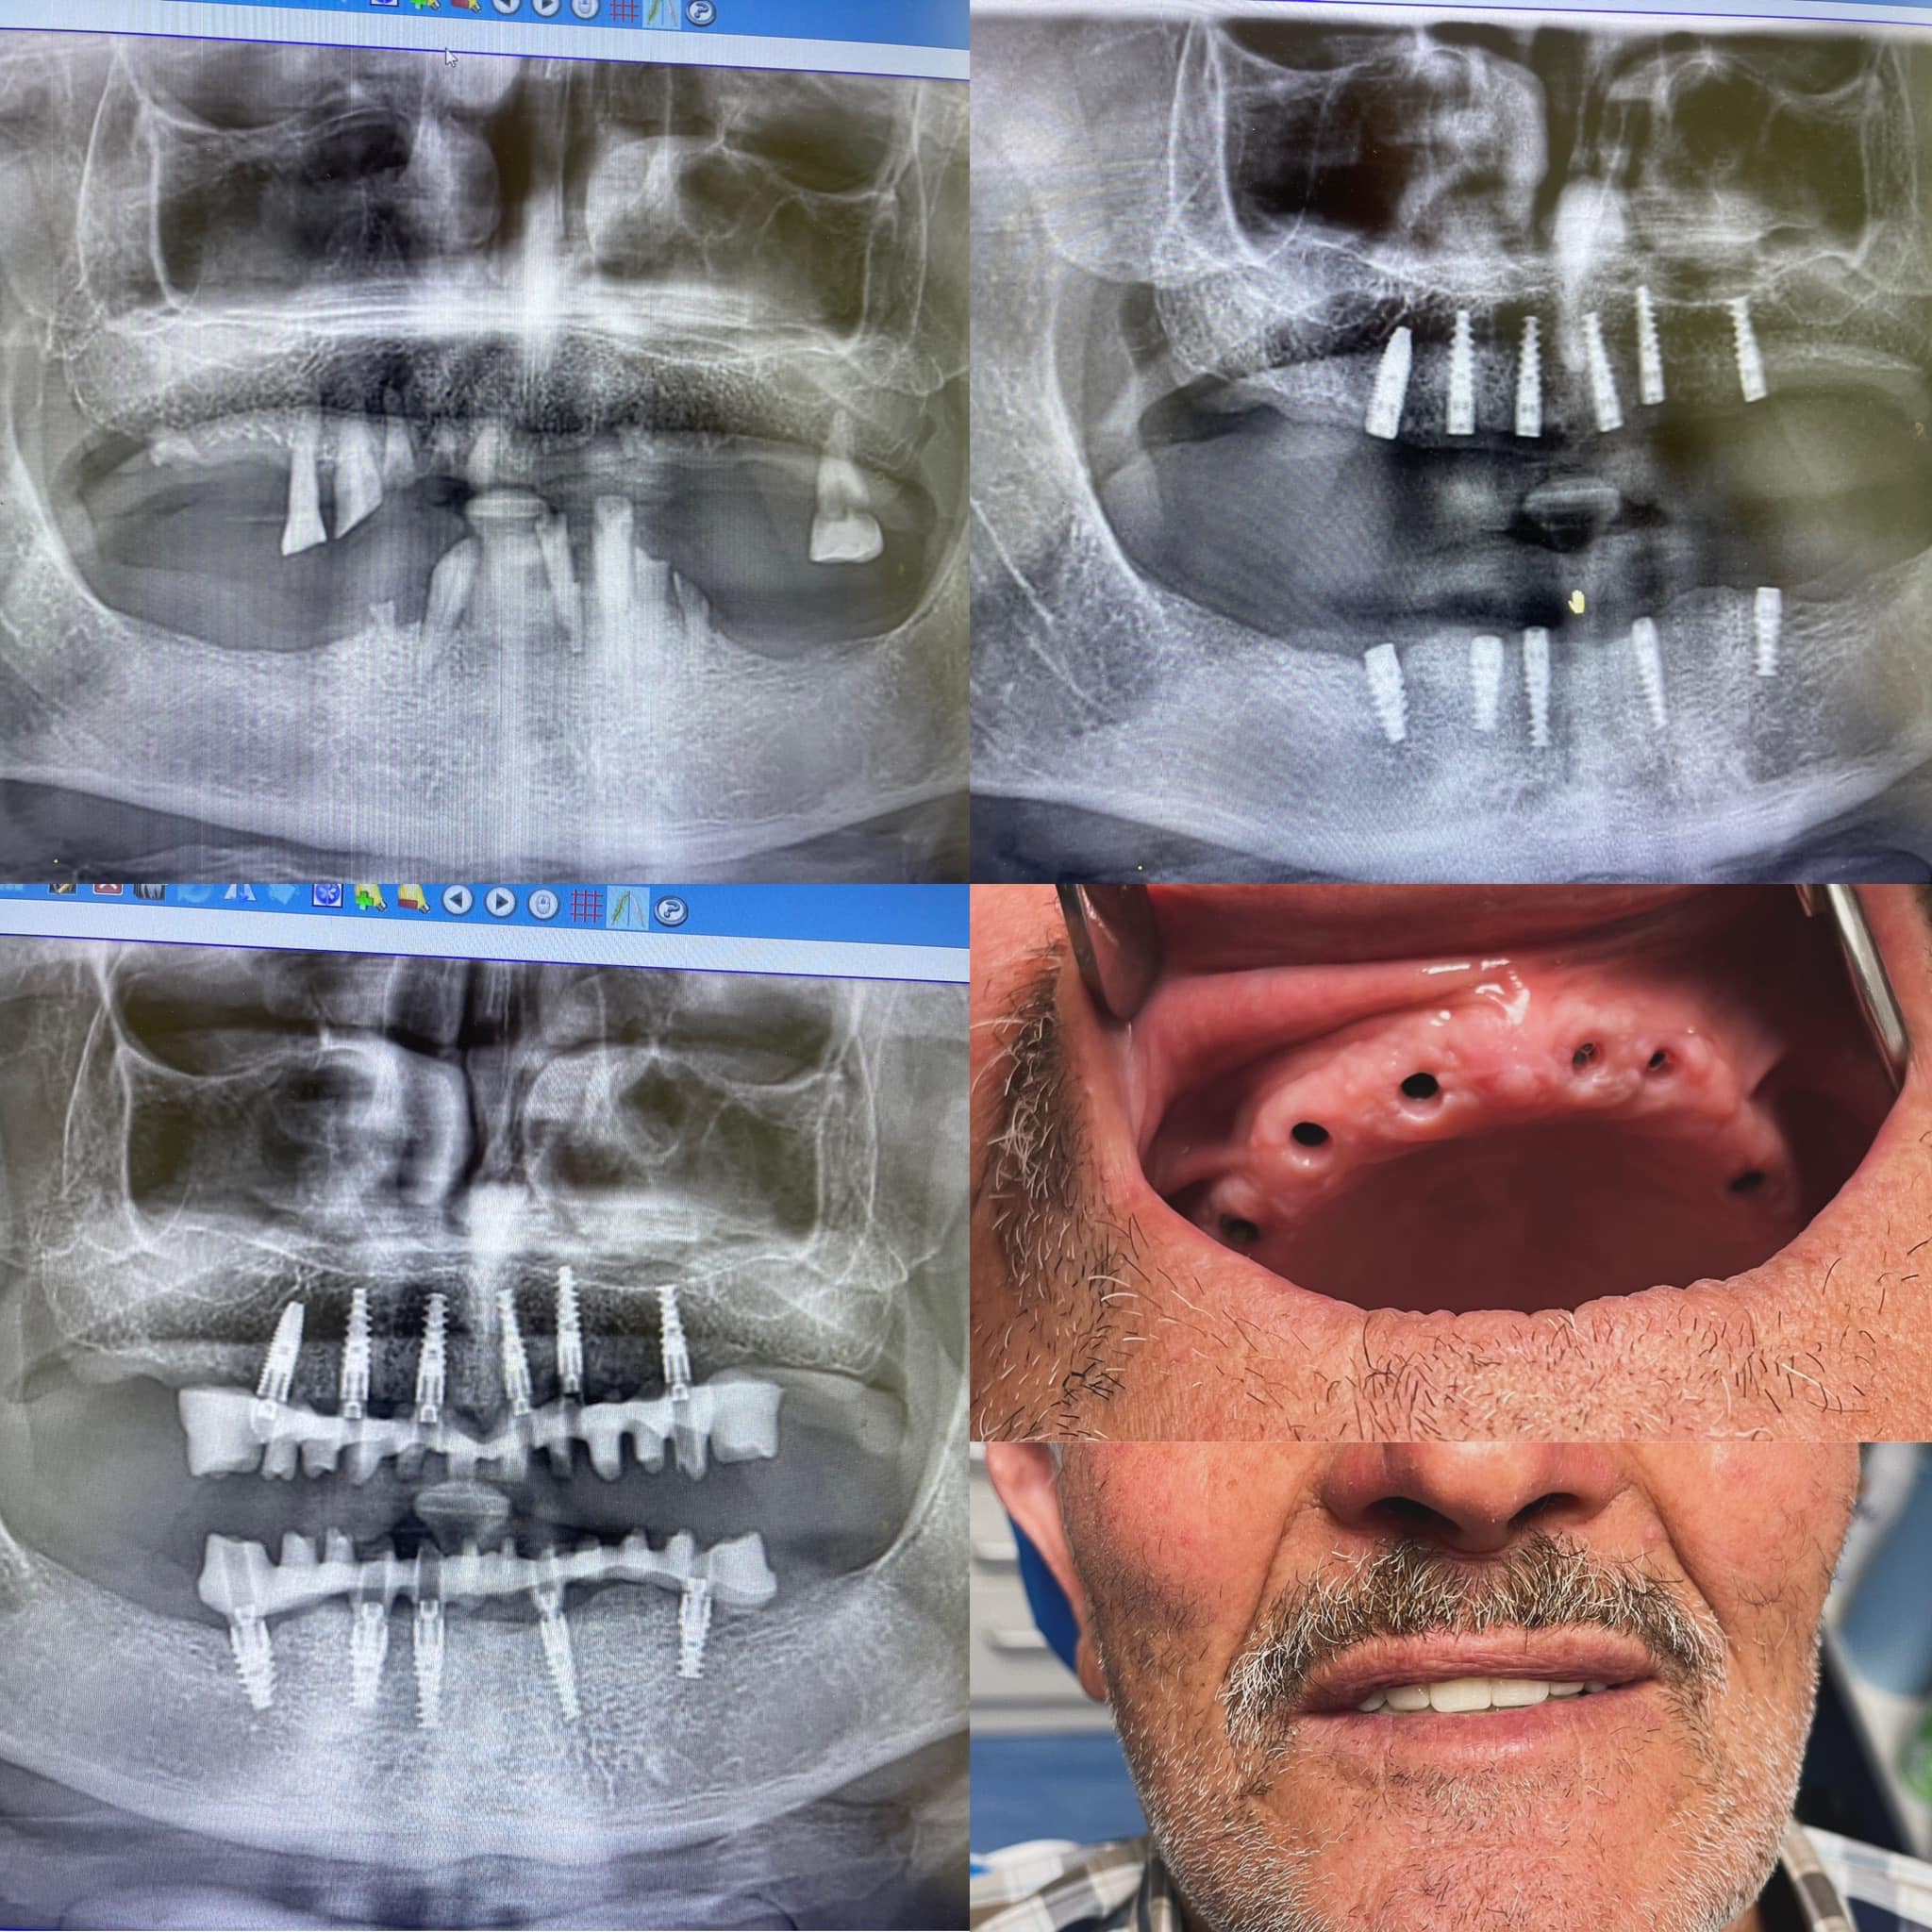

L’intervento ha previsto il posizionamento di impianti dentali Nobel Biocare, una delle soluzioni più avanzate e affidabili nel campo dell’implantologia.

Prima: il paziente presentava la mancanza di uno o più denti, con conseguente difficoltà masticatoria e impatto estetico sul sorriso.

Dopo: grazie all’implantologia, i denti sono stati sostituiti con protesi fisse supportate dagli impianti, ripristinando funzionalità ed estetica in modo naturale e duraturo.

L’uso di impianti Nobel Biocare garantisce stabilità, biocompatibilità e risultati a lungo termine, offrendo un sorriso sano e pienamente funzionale.

Un sorriso completamente rigenerato: i denti appaiono perfettamente allineati, naturali e luminosi, con un aspetto armonioso e funzionale.

Il risultato non è solo estetico: il sorriso è forte e stabile, permettendo una masticazione sicura e confortevole, senza compromessi sulla bellezza naturale dei denti.